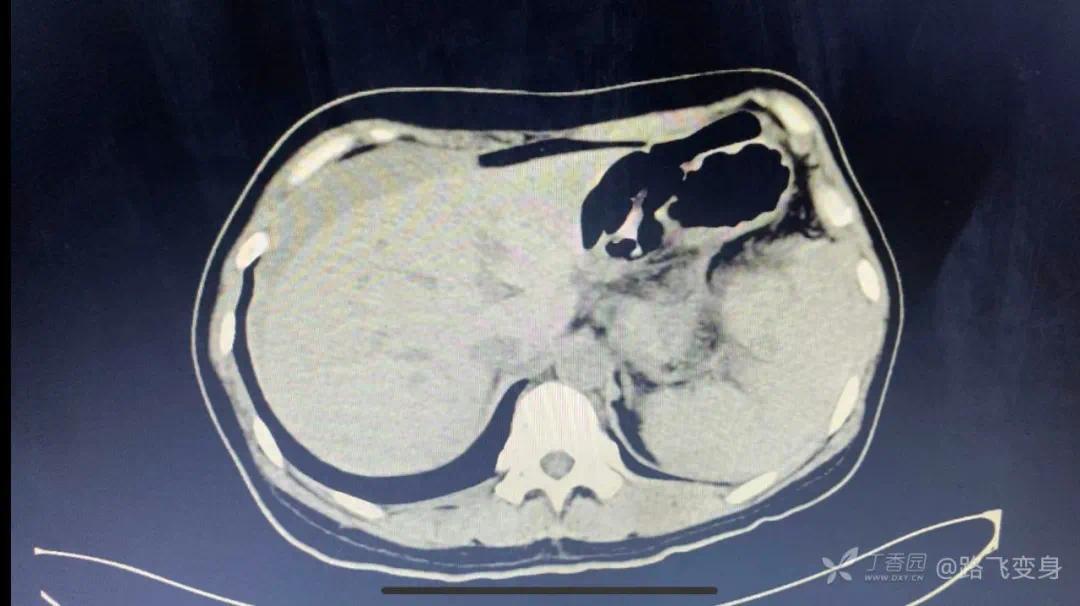

病人出现「休克」症状,没有办法只有准备手术,术前常规行全腹部 CT 检查,如下:

CT 发现明显异常。可以和下面第一次急诊 CT 视频做对比。